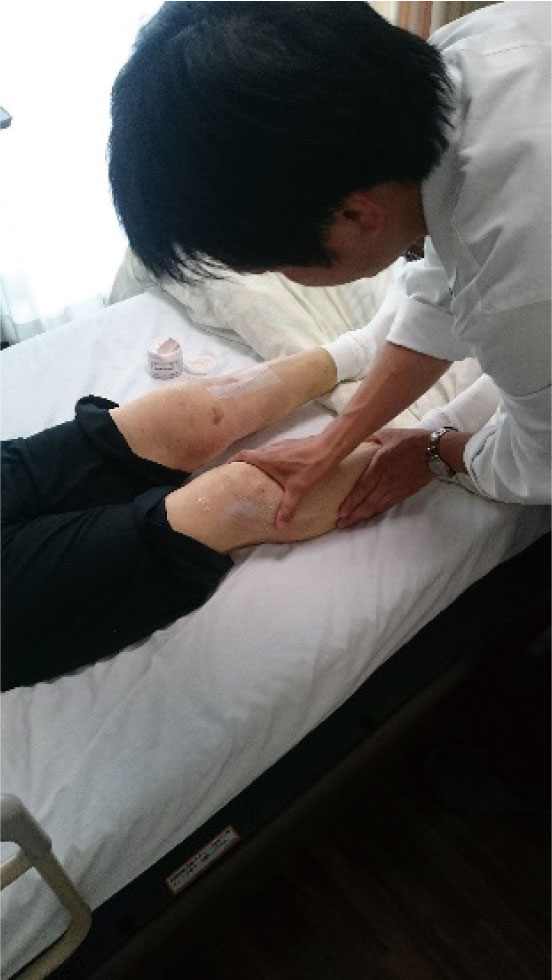

D: 手術後の患部の症状を臨床研究

協力◎石川島記念病院整形外科・千葉直樹先生(*1)

対象◎高位脛骨骨切り術(*2)の患者(16名)

内容◎同じ手術を受けた16名の患者を8名ずつに分け、一方はクリームを塗り、もう一方には塗らず、「痛み」「腫れ」「リハビリの進行度」を観察

結果◎「痛み」「腫れ」「リハビリの進行度」において、クリームを塗ったグループの優位性を確認

この臨床研究は、千葉先生のもと高位脛骨骨切り術を施術された患者さん(61~78歳の女性16名)を対象に実施。術後一週間が経過して抜糸をした後、両脚にそれぞれ3分ずつクリームを使ったマッサージを毎日施したグループと施していないグループとを比較。比較した内容は、「痛み」「腫れ」「リハビリの進行度」の3点。

クリームで軽いマッサージを施したところ、患者さんたちから高評価をいただきました。また、塗る時間は、患者さんと医師とのコミュケーションの時間にもなります。お互いの信頼も増していくという効果もあり、不満も減ってリハビリへの意欲も増していくと考えます。